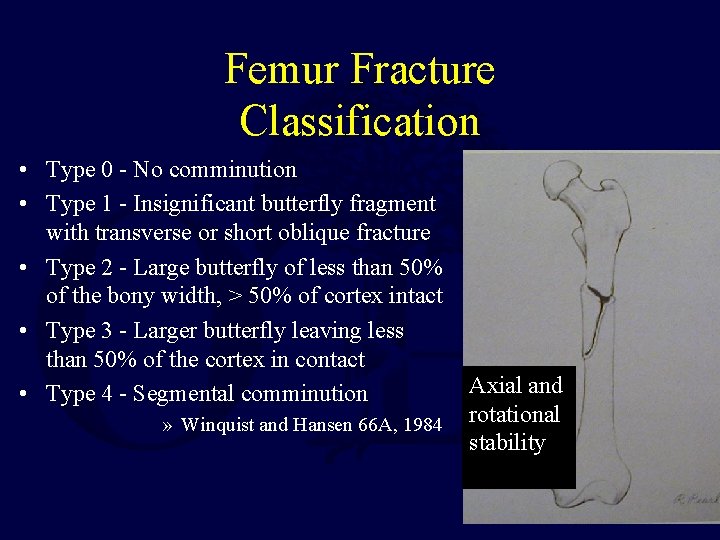

Femur Fracture Classification • Type 0 - No comminution • Type 1 - Insignificant butterfly fragment with transverse or short oblique fracture • Type 2 - Large butterfly of less than 50% of the bony width, > 50% of cortex intact • Type 3 - Larger butterfly leaving less than 50% of the cortex in contact • Type 4 - Segmental comminution » Winquist and Hansen 66 A, 1984 Axial and rotational stability